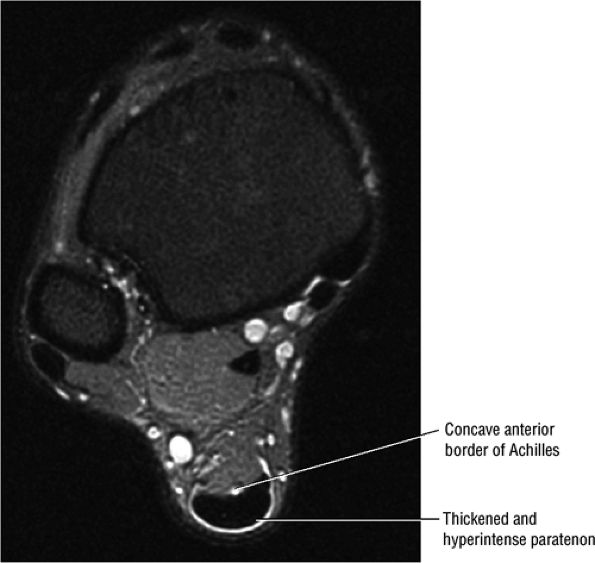

-

The Achilles tendon has no synovial sheath but is associated with a paratenon or connective tissue envelope.

In paratendinitis (also known as peritendinitis, since it refers to the peritendinous tissues), there is generalized inflammation of the tissues surrounding the Achilles tendon (pre-Achilles fat).32

In paratendinitis (peritendinitis) (Fig. 5.106) with tendinosis, there is inflammation of the surrounding tissues with associated tendon degeneration.

The paratenon (also referred to as the peritenon) represents the connective tissue envelope surrounding the Achilles tendon.

Paratenonitis is an inflammation of the Achilles tendon connective tissue envelope (usually limited to the posterior paratenon on MR images).

An irregular pre-Achilles fat pad may be seen with paratendinitis (peritendinitis) with or without abnormal Achilles tendon morphology.

Increased cross-sectional diameter on axial images

Increased anteroposterior dimensions

Prominent anterior convexity with focal or diffuse thickening in the sagittal plane

Thickening and intermediate signal of peritendinous tissue dorsal, medial, and lateral to the Achilles tendon on T1- or PD-weighted images

Intermediate-signal-intensity effacement of peritendinous tissue anterior to the Achilles tendon on T1- or PD-weighted images

Hypointense to intermediate signal within an enlarged tendon in hypoxic fibromatosis (Fig. 5.111) on FS PD FSE images

Inflammatory fluid anterior to the tendon and proximal extension of fluid in the retrocalcaneal bursa

Myxoid degeneration (Fig. 5.112) with increased signal on FS PD FSE or STIR images

Calcific (Fig. 5.113) or ossific degeneration with tendon thickening

Associated partial tears

Enthesopathic insertional tendinitis (Fig. 5.114)

Haglund's deformity (Figs. 5.115, 5.116, and 5.117) (insertional tendinitis with reactive calcaneal marrow edema [see Fig. 5.116], and the constellation of thickened tendon, retrocalcaneal/tendo Achilles bursitis, and a calcaneal bony prominence)

Effacement and edema of the pre-Achilles fat body with normal tendon morphology and/or signal